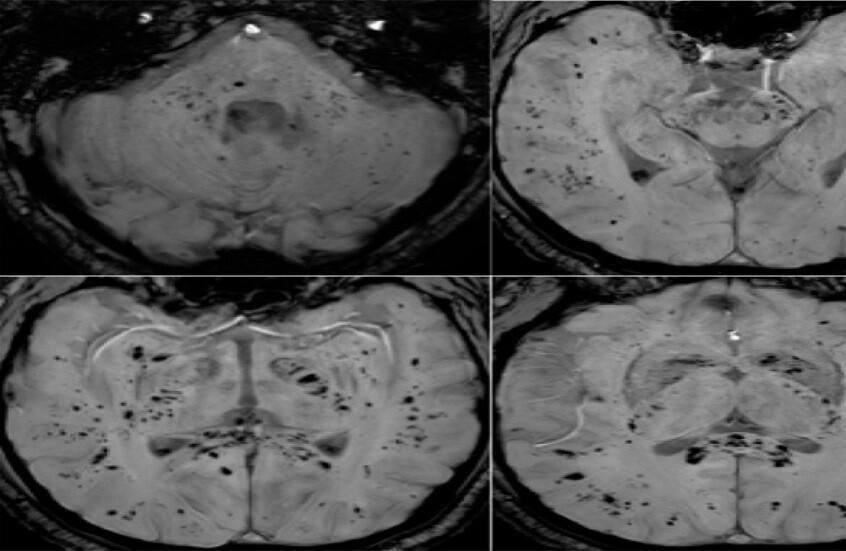

تحليل بالرنين المغناطيسي يكشف تأثير كوفيد-19 المستمر على الدماغ

أظهر تحليل صور بالرنين المغناطيسي أن فيروس كوفيد-19 يترك أثرا لا يُمحى في الدماغ، ويستمر تأثيره حتى بعد التعافي التام.   أظهرت دراسة حديثة أجراها علماء في جامعة غريفيث الأسترالية ونُشرت في مجلة Brain, Behavior, & Immunity Health أن فيروس كوفيد-19 لا يؤثر على الجهاز التنفسي فحسب، بل يترك أثرا …

دراسات علمية جديدة تكشف أن فيروس كوفيد-19 يغيّر وظائف الدماغ حتى بعد التعافي

كشفت دراسة علمية جديدة أجراها باحثون من المركز الوطني لعلم المناعة العصبية والأمراض الناشئة بجامعة غريفيث أن الإصابة بفيروس كوفيد-19 قد تؤدي إلى تغيّرات مستمرة في وظائف الدماغ، حتى بعد التعافي السريري الكامل من المرض.   وأظهرت النتائج، التي نُشرت في مجلة علمية متخصصة، أن العدوى تترك آثارا قابلة للقياس في الجهاز …